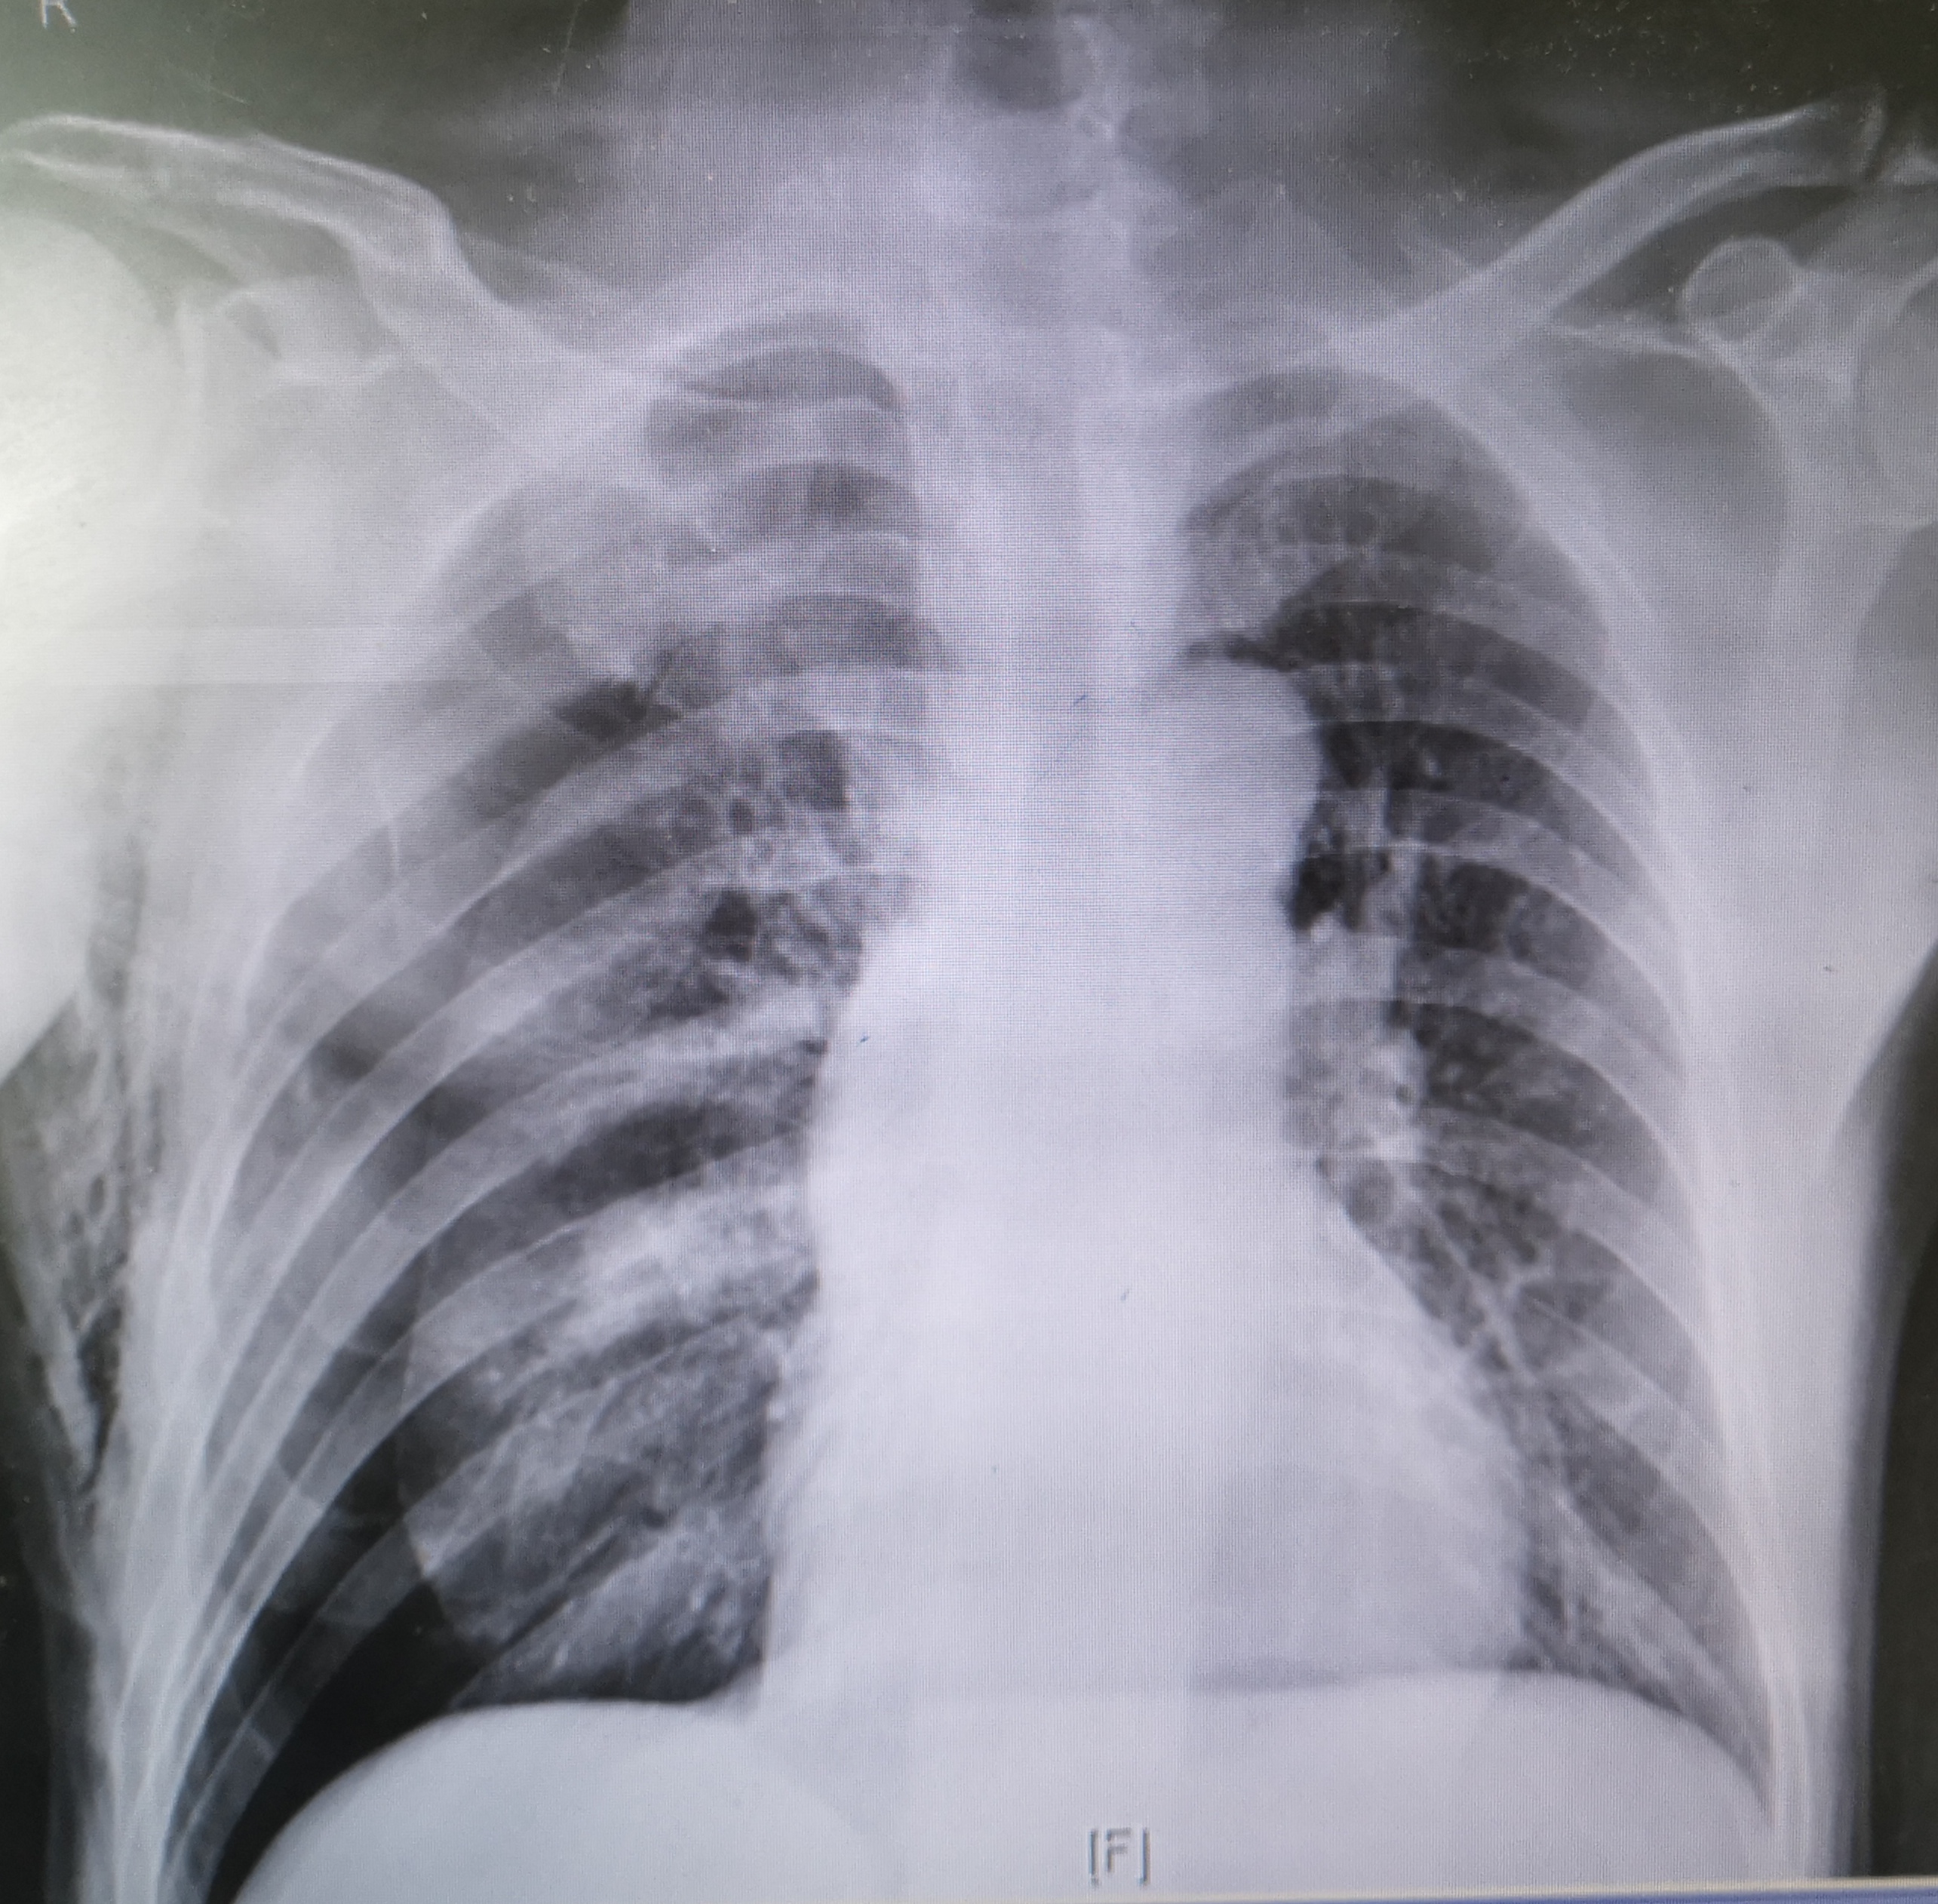

桶状胸,胸廓接近正方形,提示明显的肺气肿

右肺被压缩了50%以上

胸部x线片是诊断气胸最简单也最快捷的方法,既能够确诊气胸,也能够显示出气胸的量和肺脏受压迫的程度。一般来说,肺压缩20%以下的小量气胸,患者如果没有明显胸闷、呼吸困难症状,可以不做特殊的处理,让病人平卧、吸氧气,不要做用力的动作就可以了,胸腔内的少量气体会自行慢慢吸收。但是如果气胸量比较多,肺部受压明显,或者病人的症状比较明显,则需要做胸腔穿刺或者胸腔闭式引流术,将气体抽出来。